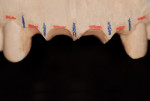

A 68-year-old woman was treated for severe localized adult periodontitis affecting the esthetic zone. Her chief complaint was the presence of spaces between her teeth and the unpleasant shape of the anterior maxillary dentition. The periodontal disease had disrupted the osseous and gingival architecture, causing tooth migration, supraeruption, mobility, flaring, and diastemas (Figure 4). Periapical radiographs showed severe bone loss and an unfavorable crown-to-root ratio (Figure 5).

Two weeks after the extractions, the gingival component had already regained a sharp positive architecture (Figure 12). The challenge would have been preserving it over time.